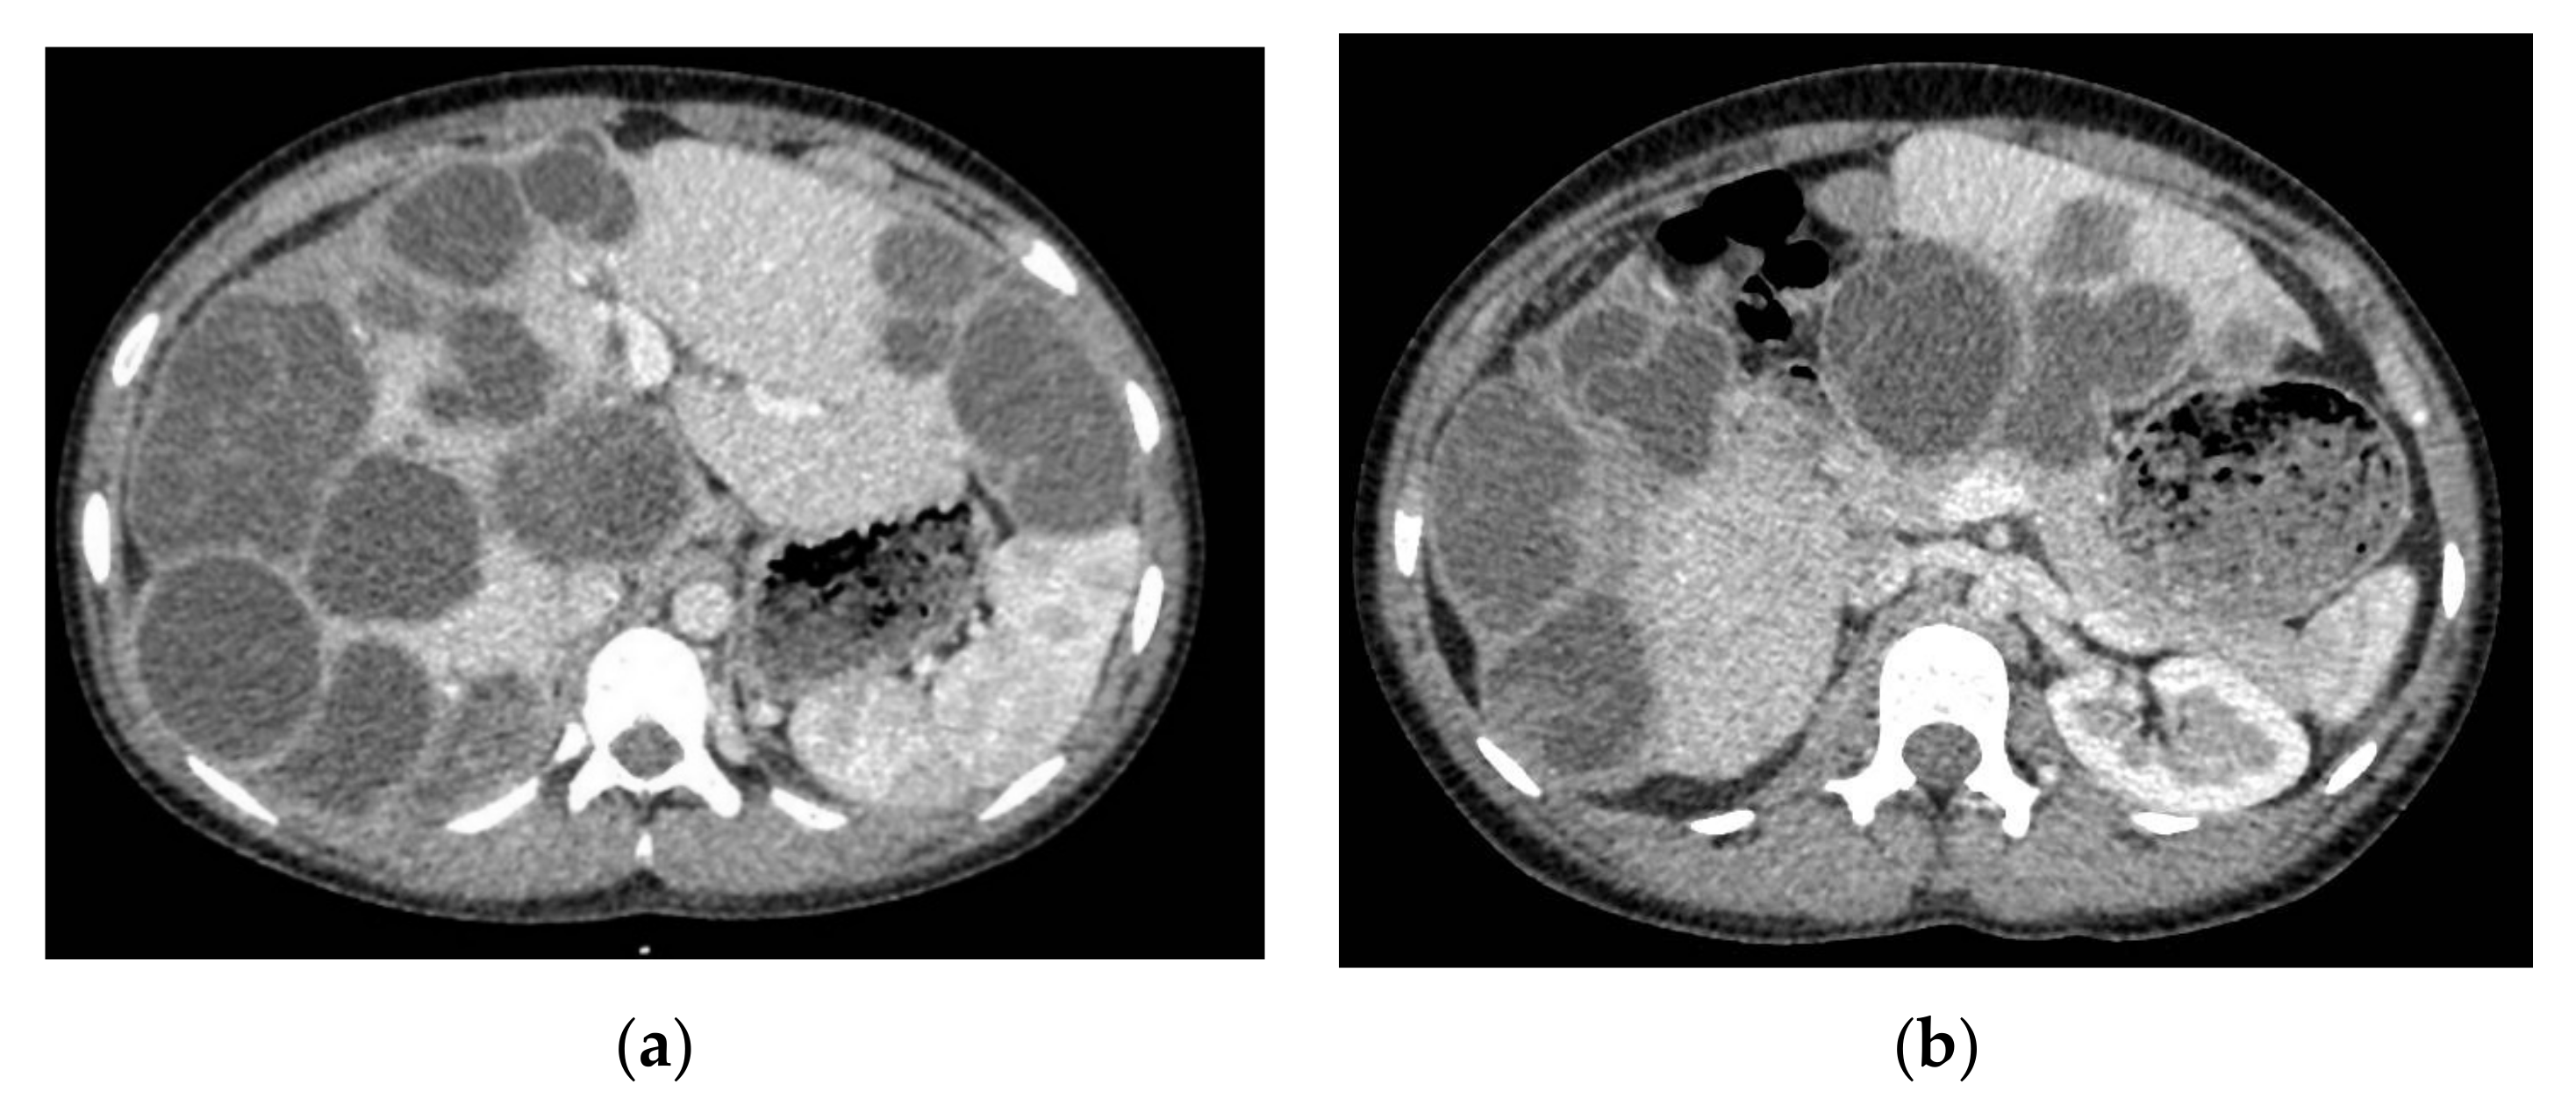

A head computed tomography (CT) Scan with intravenous (IV) contrast (Figure 2 and Figure 3) showed a huge left frontal cyst, with a fine wall and a fine septum inside, minimum peripheral load, left frontal osteolysis, moderate peripheral edema, edematous optic nerves (bilateral secondary papillary edema). Cranio-cerebral magnetic resonance imaging (MRI) examination with contrast (Figure 4) supported the diagnostic suspicion of a cerebral hydatid cyst. Cystic lesions with membranes and daughter cysts are highly probable to be hydatid ones [7]. Based on the morphology classification, this hydatid cyst was a type IIa: a cyst with round daughter cysts at the periphery [8].

An abdominal ultrasound identified multiple hepatic cystic images, some septate, with dimensions from 30 to 60 mm. The imagistic investigation was continued with a Chest, Abdomen and Pelvic CT Scan with IV contrast, which led to identification of multiple hepatic cysts (more than 30) (Figure 5).

Figure 3. Cranial computed tomography (CT) scans with intravenous (IV) contrast. (a) axial; (b) coronal.

Figure 5. Abdominal CT Scan with IV contrast. (a,b) multiple liver cystic lesions with small areas of normal parenchyma.